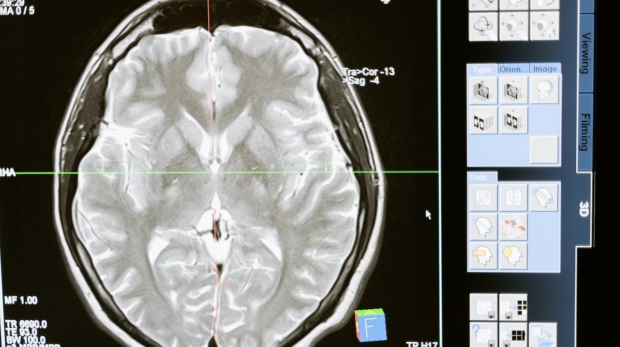

Medytacja zazwyczaj kojarzy się z praktyką duchową ściśle powiązaną z religiami Wschodu. Jednak od jakiegoś czasu stała się obiektem zainteresowania ze strony naukowców, psychologów i terapeutów jako zaskakująco skuteczna metoda poprawy zdrowia i samopocz ...